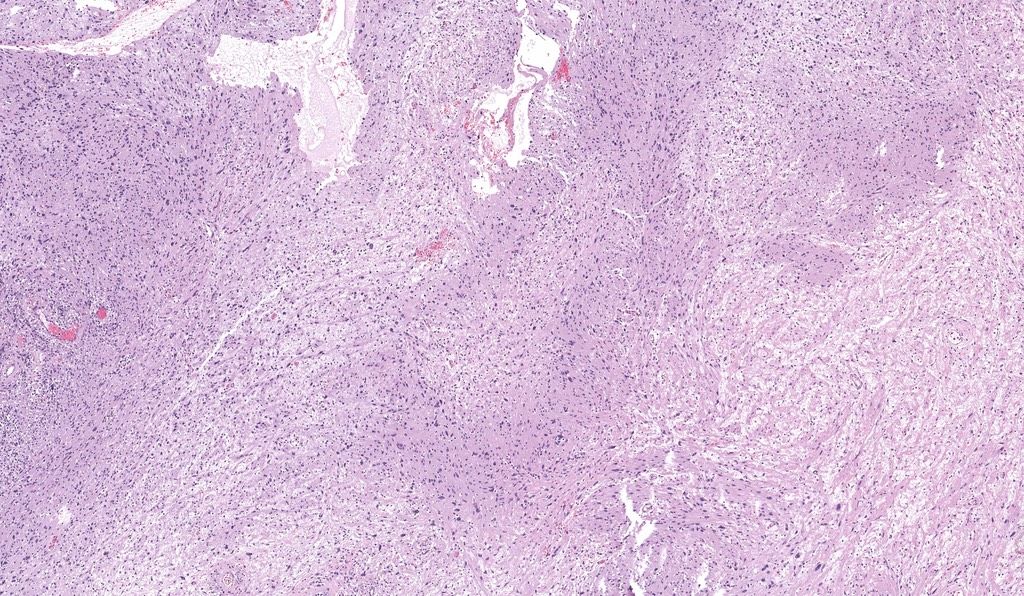

Based on just histology and epidemiology,

This 75 y/o M

Likely has metastatic ___________

#pathx #dermpath #pathology #path4people #pathagonia